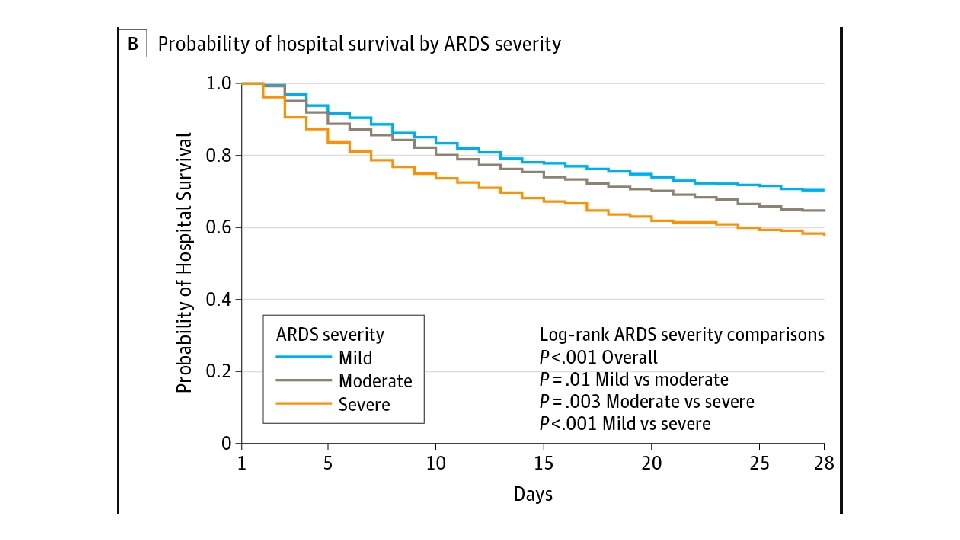

• • • International Study involving 29, 144 patients 10% of all patients admitted to ICU had ARDS 23% of mechanically ventilated patients had ARDS Mortality in the subgroup of patients with severe ARDS was 46% Patients who survive are at high risk for cognitive decline, depression, PTSD, and persistent skeletal muscle weakness

Acute Respiratory Distress Syndrome • Highest rates reported in Australia and the USA • Underuse of currently recommended lung-protective practices was seen across the severity spectrum